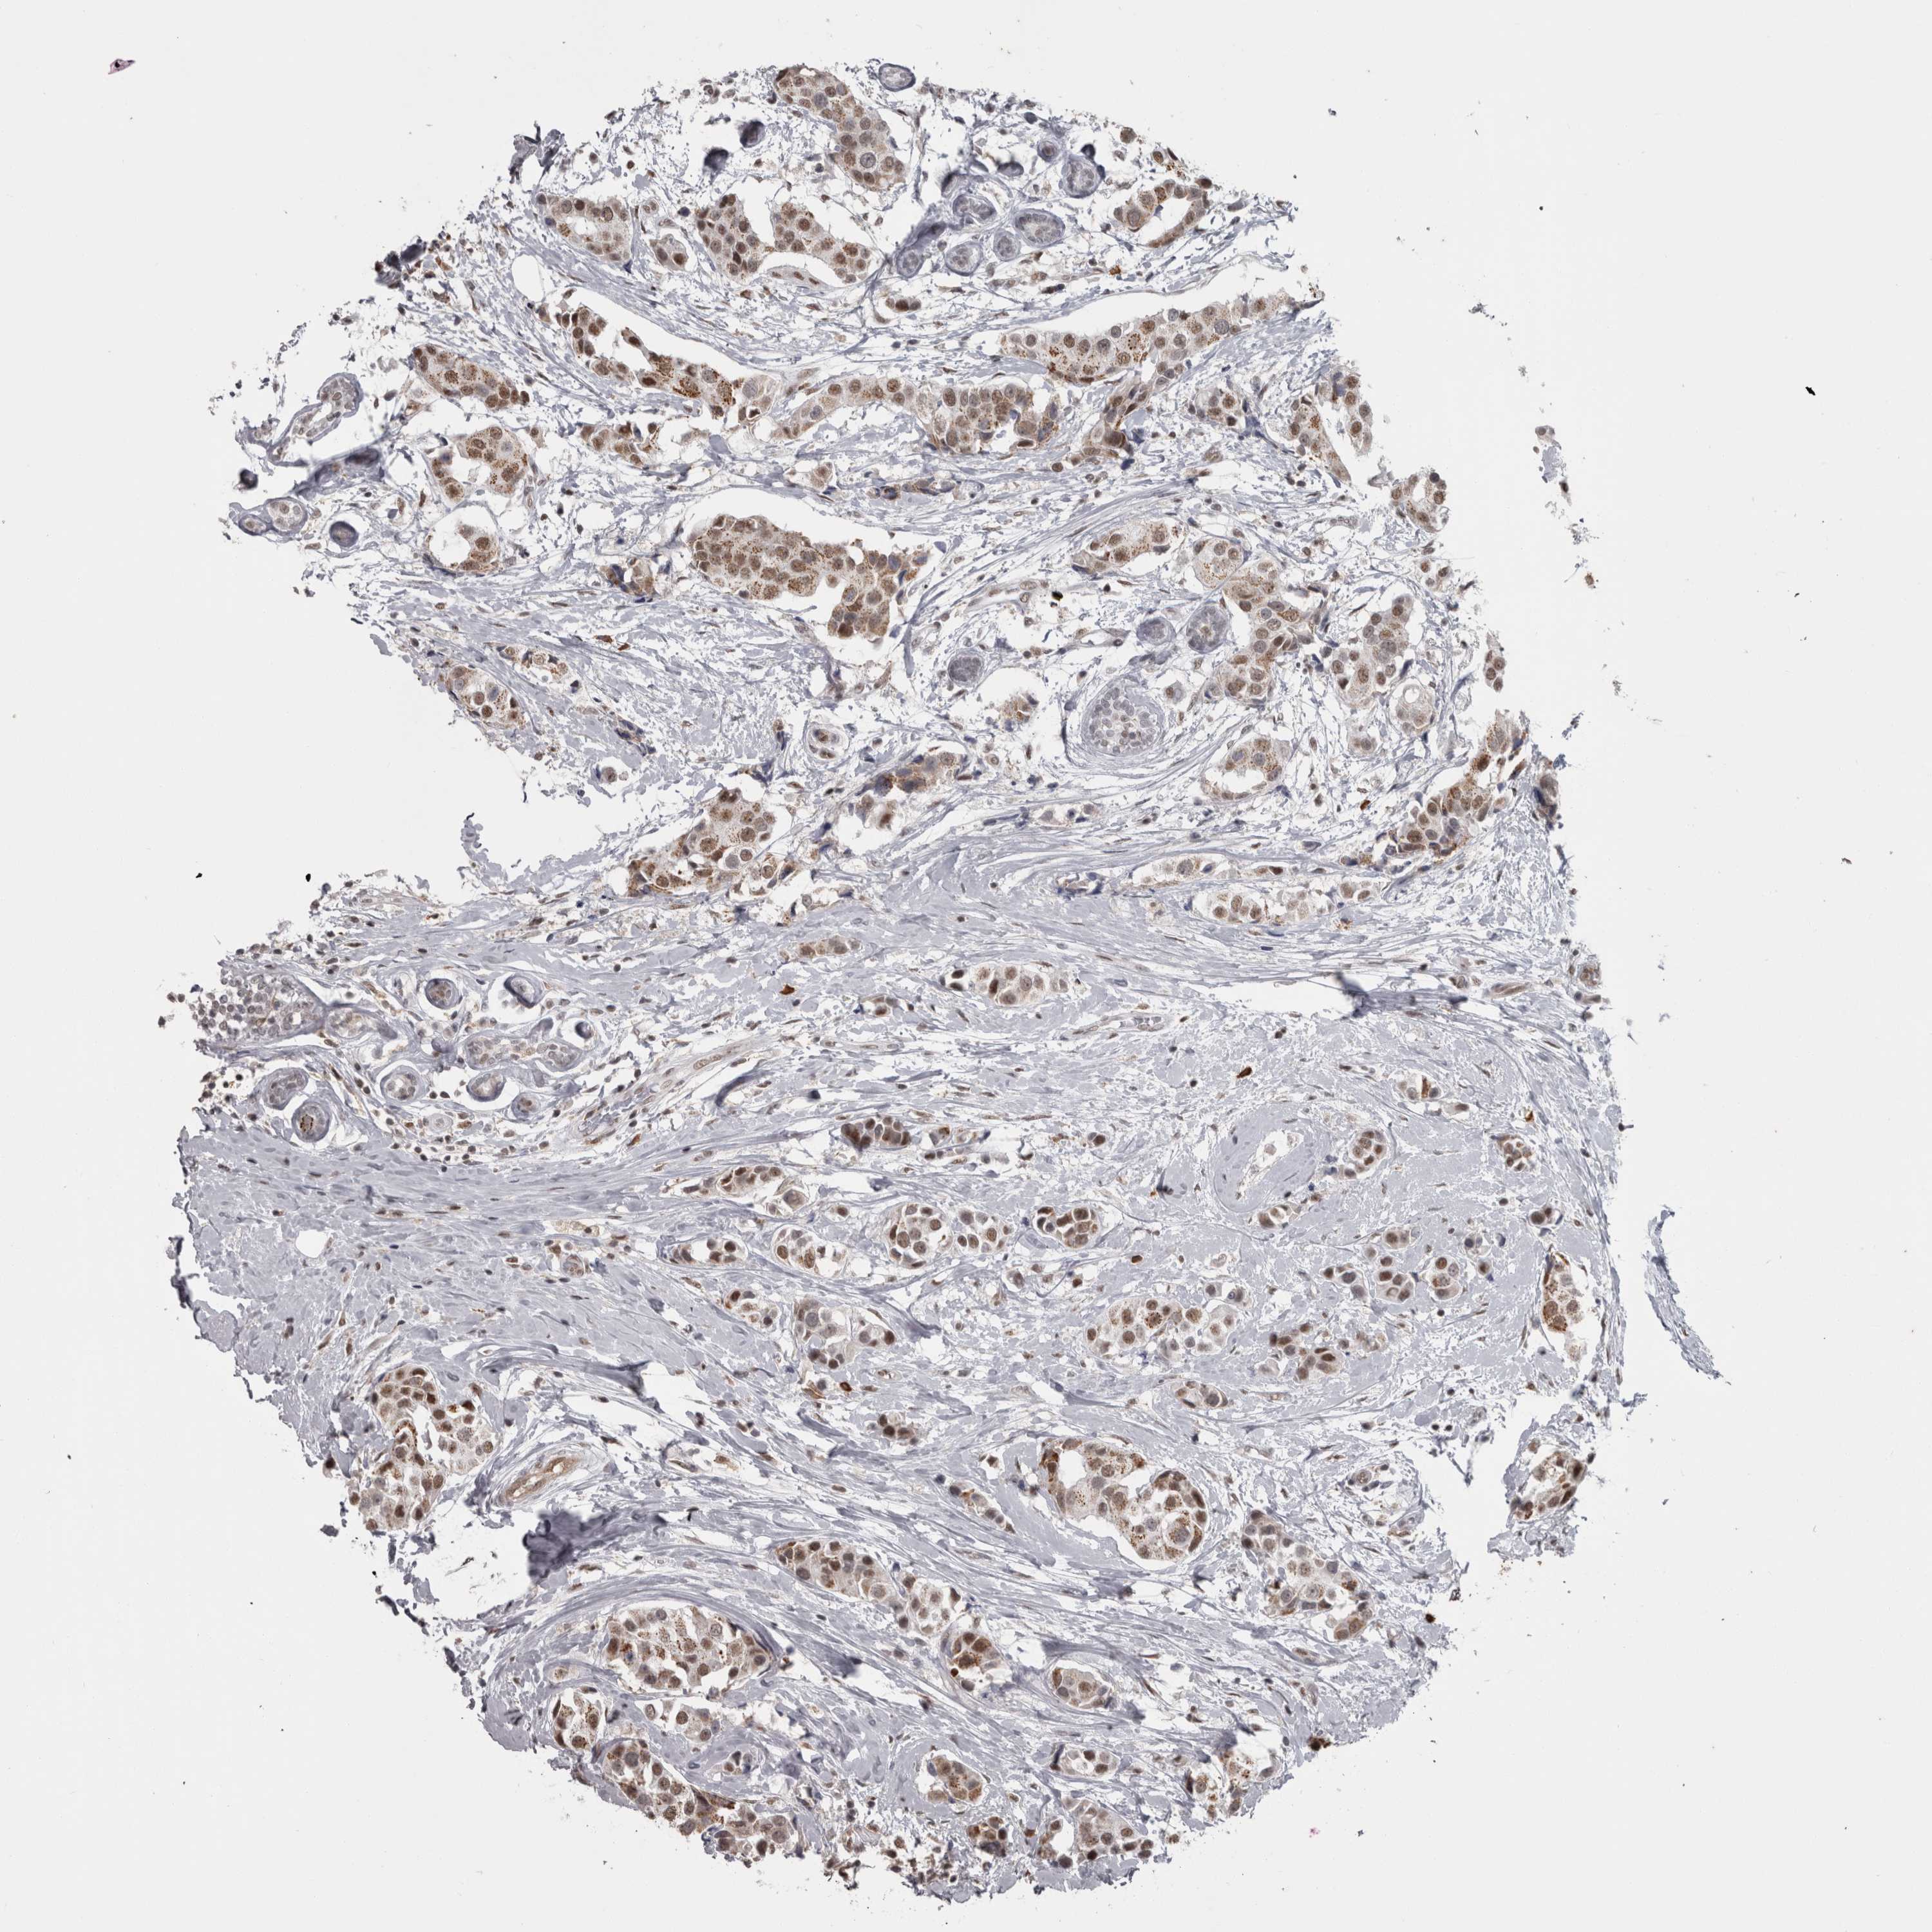

CANCER BREAST CANCER Show tissue menu

BRCA TCGA BRCA VALIDATION PROTEIN EXPRESSION